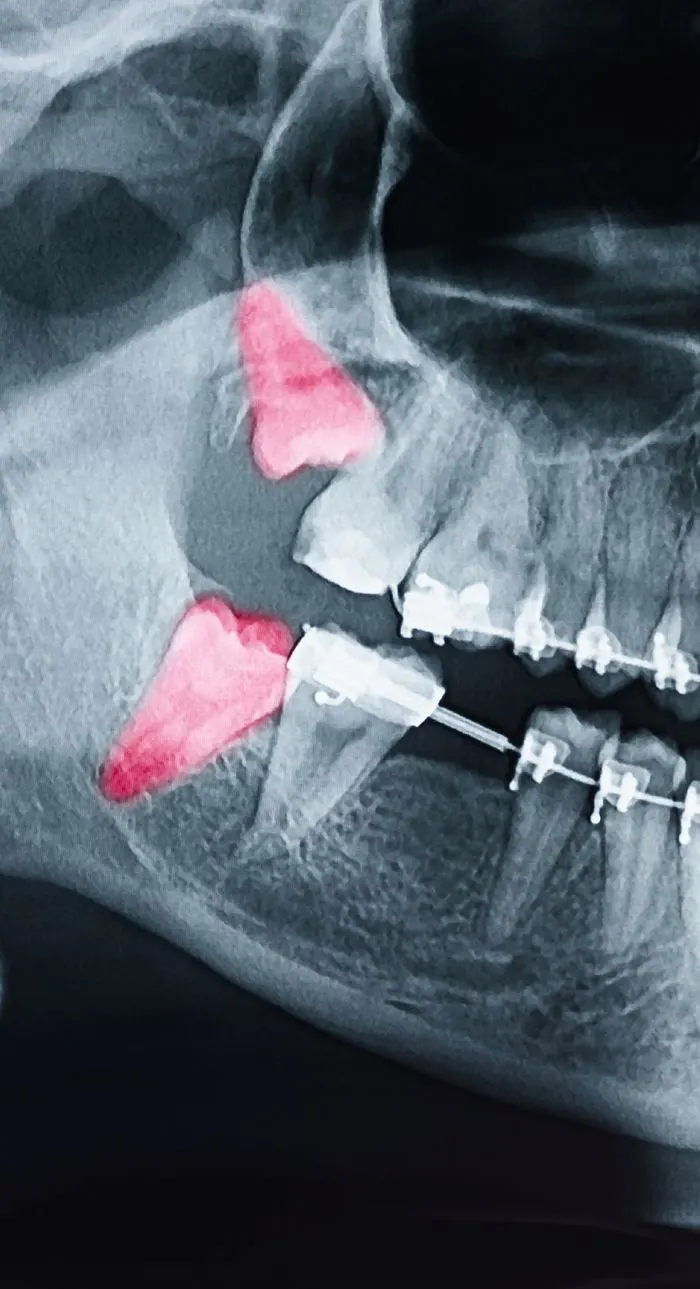

With digital x-rays, we get high-resolution images of your teeth that allow us to make more accurate diagnoses. When you’re in pain or experiencing an emergency, we can see why the tooth is reacting and if an extraction is needed.

During your consultation, we’ll take digital x-rays to assess the condition of your tooth and the surrounding bone. We’ll explain whether extraction is truly necessary and walk you through any alternatives. If you’re moving forward, we’ll review the number of teeth to be removed, aftercare expectations, and any follow-up recommendations for tooth replacement. We’ll answer every question you have so you feel fully informed and know what to expect.

Tooth extractions are typically recommended when a tooth is beyond repair due to severe decay, advanced gum disease, trauma, or infection. Sometimes, a tooth may need to be removed to make room for orthodontic treatment or to prepare for a dental implant or denture.

Wisdom teeth are often extracted if they’re impacted, causing pain, or crowding surrounding teeth. Your dentist will always explore all options before recommending removal, but sometimes extraction is the best way to protect your long-term oral health.